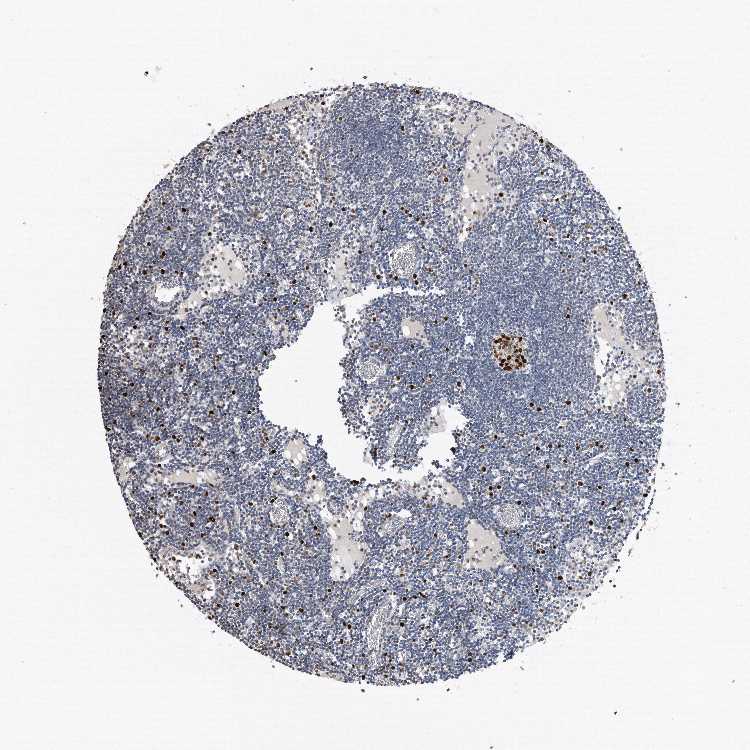

TISSUE PRIMARY DATA LYMPH NODE Show tissue menu

Lymph node

LYMPH NODE - Antibody stainingi

Antibody staining in the annotated cell types in the current human tissue is reported as not detected, low, medium, or high, based on conventional immunohistochemistry profiling in selected tissues. This score is based on the combination of the staining intensity and fraction of stained cells.

Each image is clickable and will lead to virtual microscopy that enables deeper exploration of all samples and also displays staining intensity scores, fraction scores and subcellular localization as well as patient and tissue information for each sample.

Antibody HPA030521Antibody HPA030522Antibody HPA030523Antibody CAB000148Antibody CAB080240Antibody CAB080241Antibody CAB080242

Germinal center cells HighHighHighMediumHighHighHigh

Non-germinal center cells MediumMediumMediumLowMediumMediumMedium